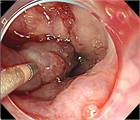

1. 食道・胃静脈瘤は慢性肝疾患などによる門脈圧亢進症に伴って代償的に形成される側副血行路の1つである。

1. 食道静脈瘤:内視鏡的硬化療法(EIS)、内視鏡的静脈瘤結紮術(EVL)を行う。

1. 胃静脈瘤:内視鏡的塞栓術(Histoacrylによる)、バルーン閉塞下逆行性経静脈的塞栓術(balloon-occluded retrograde transvenous obliteration:B-RTO)を行う。